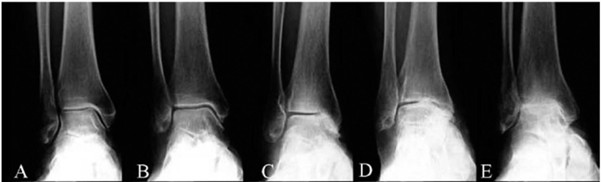

O diagnóstico por imagem é baseado em radiografias em carga, em que se visualiza o estreitamento do espaço articular, esclerose do osso subcondral, formação de osteófitos e possíveis deformidades articulares. A artrose do tornozelo pode passar despercebida nos estadios iniciais com as radiografias, podendo nestes casos ser necessário o estudo complementar com tomografia computorizada ou ressonância magnética.